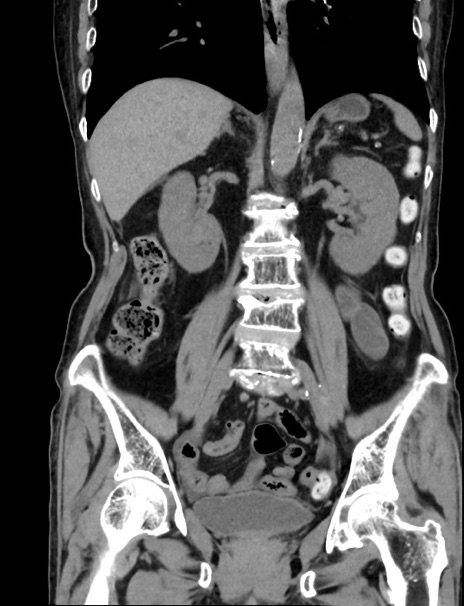

症例33(冠状断像)

【症例】70歳代 女性

【主訴】心窩部痛

【現病歴】延髄病変の精査・加療にて神経内科入院中。本日より心窩部痛あり。

【身体所見】右下腹部を中心に圧痛と反跳痛あり。

【データ】WBC 10900、CRP 0.02

横断像